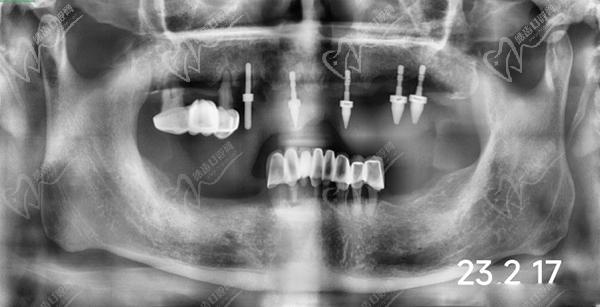

牙友1、前天結(jié)束的全口種植牙,拔牙加同期種12顆瑞士士卓曼,即刻負(fù)重!全口牙周炎伴隨多顆牙松動且骨量不足等問題,普通的種植手術(shù)無法滿足生活需求,想要做即拔即種即刻戴上臨時(shí)牙,因?yàn)槌R?guī)的植骨手術(shù)需要等待很長時(shí)間。經(jīng)過正規(guī)醫(yī)院骨質(zhì)評估分析,上頜AO4+兩邊穿翼手術(shù),患者手術(shù)結(jié)束當(dāng)天就可以正常用牙,本人表示非常高興和滿意!感謝醫(yī)院團(tuán)隊(duì)協(xié)作!

圖是我的臨時(shí)牙冠,即拔即種的牙冠都是臨時(shí)的,后期要來重新裝